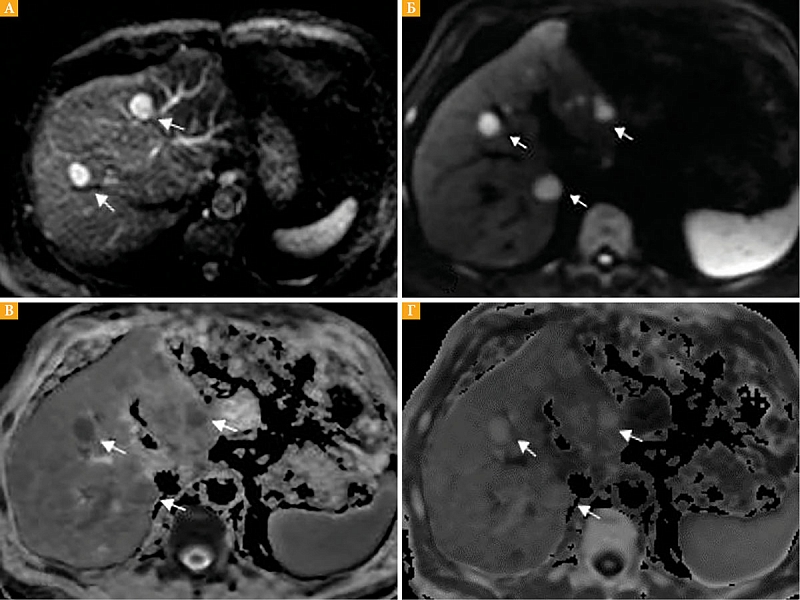

Рис. 2. Меланинсодержащий метастаз: А – на бесконтрастных Т1-ВИ с жироподавлением виден гиперинтенсивный очаг (стрелка); Б – этот же очаг (стрелка) имеет гиперинтенсивный сигнал на Т2-ВИ

Гиперинтенсивный сигнал в очагах поражения печени, как на бесконтрастных Т1-ВИ, так и на Т2-ВИ, у пяти больных мог быть обусловлен отложением меланина (рис. 2А, 2Б).

В свою очередь, один раз проведенное МРТ-исследование может быть проконсультировано разными специалистами. В частности, при МРТ брюшной полости используют стандартные импульсные последовательности Т1 и Т2 взвешенных изображений. Гиперинтенсивный очаг печени на бесконтрастных изображениях, как на Т1-ВИ, так и на Т2-ВИ, может быть обусловлен отложением меланина и является патогномоничным признаком для метастазов меланомы в дифференциальной диагностике очагового поражения печени [21, 22].

При сравнении метастазов в печени кожной и увеальной меланом было отмечено, что у пациентов с УМ более высокая экспрессия антигена MelanA, более высокое содержание меланина в клетках [23]. В этой связи логично предположить, что повышение МР-сигнала на Т1-ВИ в очаговых образованиях печени при наличии в анамнезе УМ будет патогномонично для метастазов УМ. И хотя данная сигнальная характеристика встречалась только у 5 (38,5%) из 13 обследованных нами пациентов с метастазами, она имеет решающее значение при обнаружении и дифференциальной диагностике метастатических очагов меланомы.